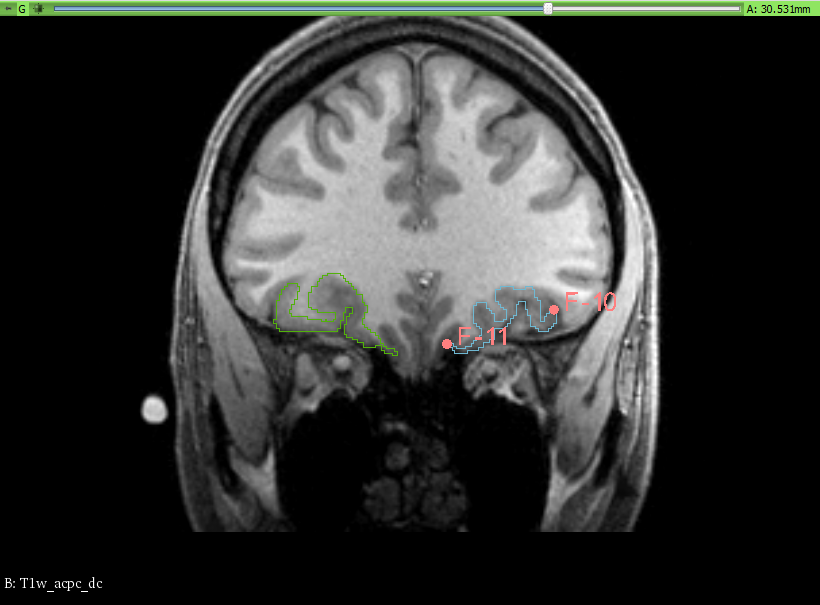

- In the OFC segment the medial and two lateral segments have been merged into a single segment. The segmentation has been done manually, tracing the contours of the desired segments between the defined anterior and posterior boundaries on the coronal view.

We have taken, for the OFC, the traditional approach, following the olfatory surcus. Fiducial points were placed on the slices for guidance.

The Slicer module used was the Segment Editor. Once the fiducial points were placed, marking the boundaries, slice by slice, the draw/paint and erase tools (with an 1 to 3% diameter) were used to manually trace and fill the corresponding areas for each segment. No other segmentation tools were used, as the work was done in an entirely manual way.

To ensure the correct overlap of the segment boundaries, when using the paint or draw tool, the setting for masking was set to editable area: outside all segments.

| Manual segmentation |